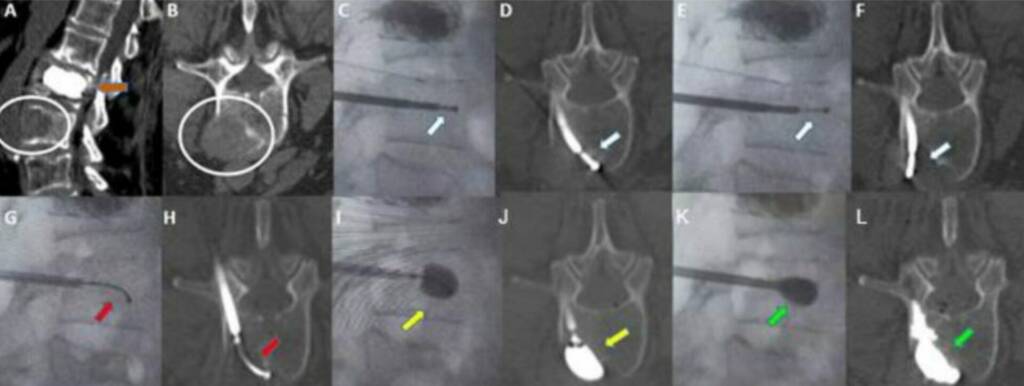

Kyphoplasty is a minimally invasive, image-guided procedure designed to stabilize vertebral fractures, relieve pain, and partially restore vertebral height.

It involves the insertion of a balloon within the vertebral body to create a cavity, followed by controlled injection of bone cement (PMMA), allowing better height restoration and reduced cement leakage compared to standard vertebroplasty.

Percutaneous transpedicular access under CT or fluoroscopic guidance

Balloon inflation within the vertebral body to create a cavity

- Controlled cement injection with real-time imaging